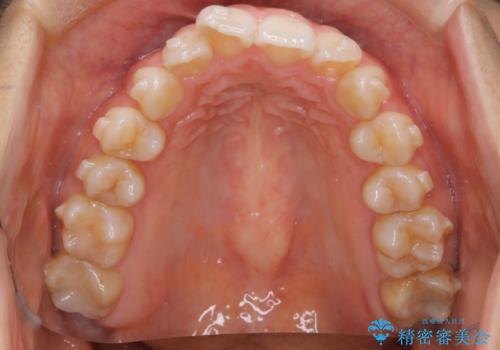

【インビザライン】前歯のねじれを治したい。

- 前歯の凸凹を主訴に来院されました。

スペースを作るために顎間ゴムを使用して、奥歯の遠心移動をおこない配列しました。

奥歯の遠心移動を行うことで、犬歯関係も良い状態に仕上げることができました。